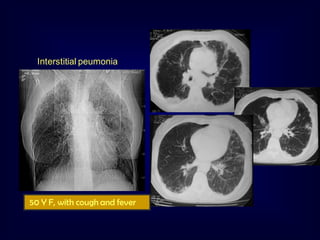

Interstitial peumonia

50 Y F, with cough and fever

• 43.

Interstitial peumonia 50 YF, with cough and fever